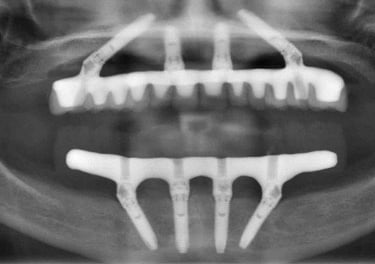

På prosedyredagen implanteres 4 implantater på passende utvalgte steder i pasientens overkjeve og/eller underkjeven. En fast bro med fullt tannsett festes på implantatene allerede på prosedyredagen. Etter et halvt år, den første (midlertidige) broen erstattes med en permanent bro forsterket med en spesiell titanbjelke (som er selvfølgelig usynlig og umerkelig).

Kirurgen plasserer 4 titanimplantater i kjevebenet og/eller underkjevebenet på punkter som er planlagt på grunnlag av tomografi.

Den midlertidige broen er skrudd på allerede på operasjonsdagen. Broen er fullt funksjonell og svært estetisk.

Spesielle koblinger er festet til implantatene, hvorpå det deretter monteres en permanent bro.

Den faste All-on-4-broen er et proteseverk laget av materialer av høyeste kvalitet, dvs. titan, porselen eller akryl av høy kvalitet. Broen er villedende lik naturlige tenner, forbedrer tale- og tyggefunksjonene betydelig og forbedrer selvfølgelig ansiktets estetikk.